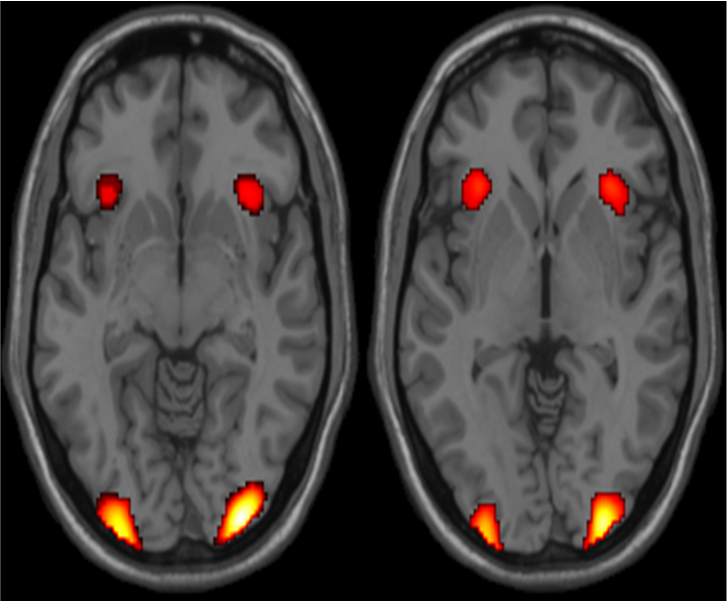

Activation of visual cortex Oxygenated and deoxygenated hemoglobin have different magnetic susceptibility. Brain tissue has a susceptibility closer to that of oxygenated hemoglobin. Therefore, with more deoxygenated hemoglobin in the blood, there is less disturbance in the magnetic fields and the spinning water molecules exposed to the magnetic fields see less difference in spin velocity between positions. As a result the net spin vector of the molecules stays larger and is measured as a larger MRI signal. Thus, blood with a greater fraction of oxygenated hemoglobin sees a larger signal. This corresponds with a greater fraction of oxygenated hemoglobin in active neurons.